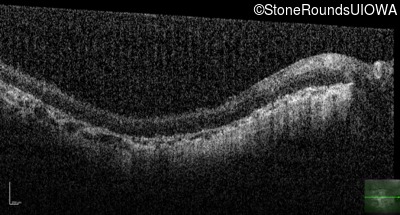

Optical Coherence Tomography - Right - Hand Motion sc

Exemplar / OCT Stack